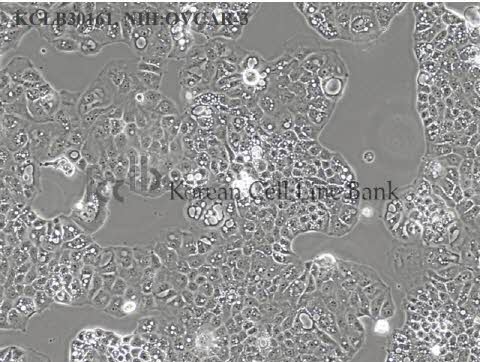

NIH:OVCAR-3

30161

| Origin |

ovary

| Species |

human female, 60 years, Caucasian

| Cellular morphology |

epithelial

| Growth Pattern |

monolayer

| Histopathology |

adenocarcinoma